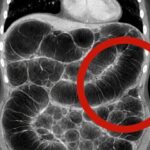

Frequent intestinal gas: the real causes that almost no one explains clearly

1. Overview of Frequent Gas and Bloating Experiencing constant intestinal gas can be uncomfortable and frustrating. While many people blame their diet alone, the issue is often tied to how the digestive system functions overall. It’s not just about what you eat—but how your body processes it. 2. Poor Digestion as a Key Cause One of the most common reasons is … [Read more...] about Frequent intestinal gas: the real causes that almost no one explains clearly